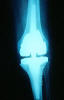

Prótesis completa de rodilla. Situación postquirúrgica.

Prótesis completa de rodilla. Situación postquirúrgica. Lateral.

Prótesis completa de rodilla.Lateral.

Prótesis completa de rodilla. Frontal.